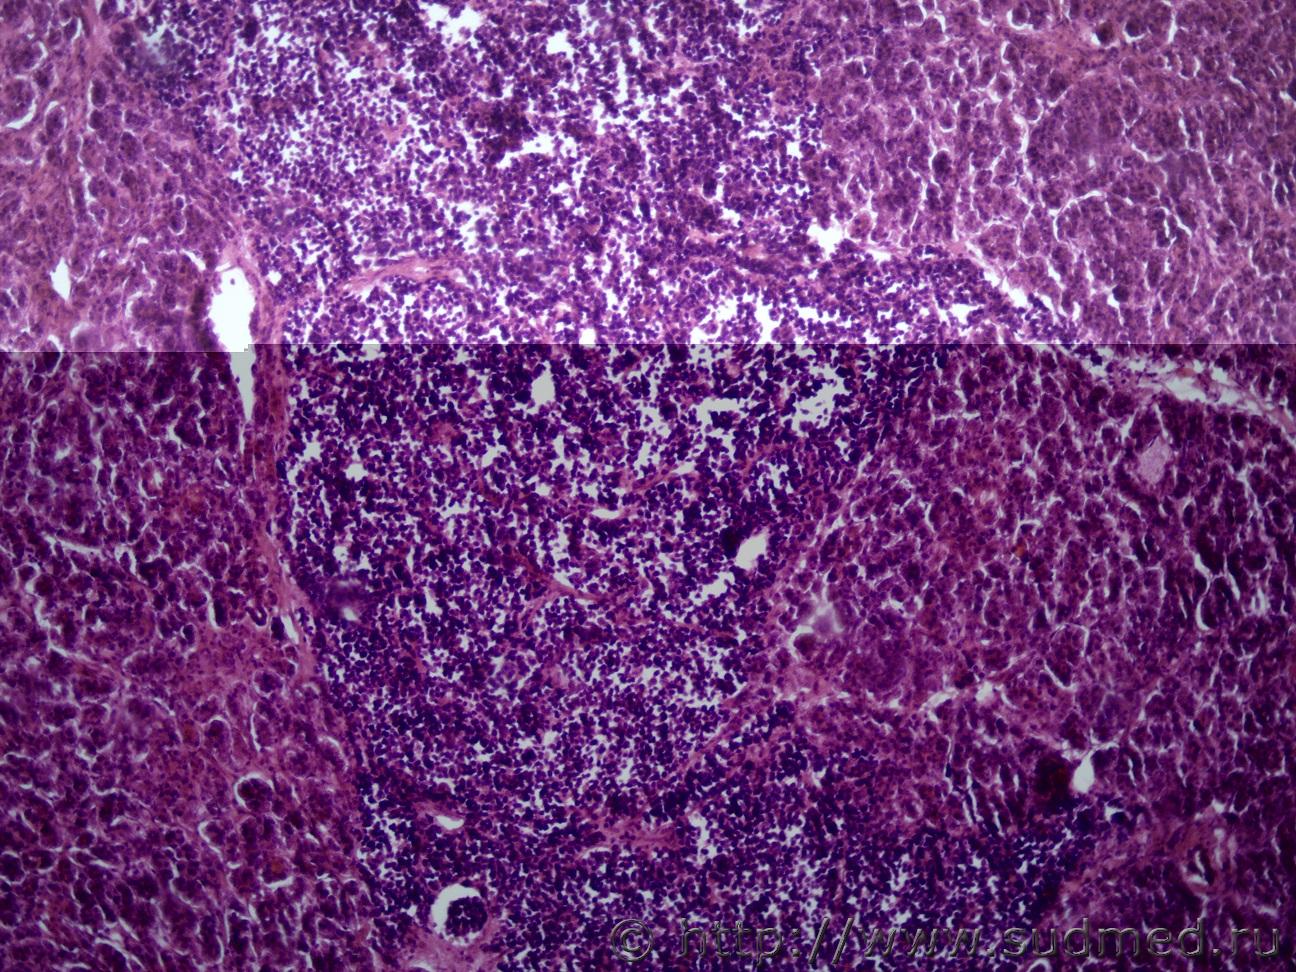

Ув. коллеги и снова здравствуйте. Как всегда опухоль. Макро- опухоль поджелудочной железы с прорастанием в окружающую клетчатку с метастазами в перибронхиальные, перипортальные ЛУ, в прикорневые отделы легких, в стенку желчного пузыря, тонкого кишечника. Легкие Судебная медицина - Прикрепленное изображение Судебная медицина - Прикрепленное изображениеСудебная медицина - Прикрепленное изображениеСудебная медицина - Прикрепленное изображение, перибрЛУСудебная медицина - Прикрепленное изображение ПЖ Судебная медицина - Прикрепленное изображениеСудебная медицина - Прикрепленное изображение , печеньСудебная медицина - Прикрепленное изображение Судебная медицина - Прикрепленное изображение Судебная медицина - Прикрепленное изображение Судебная медицина - Прикрепленное изображение Судебная медицина - Прикрепленное изображение, тонк кишСудебная медицина - Прикрепленное изображение

Наиболее подходит нейроэндокринный рак

Спасибо, рассмотрю этот вариант. Я все думала может НД протоковая аденокарцинома или мелкоклеточный рак.

Солидарен.

Непохоже.